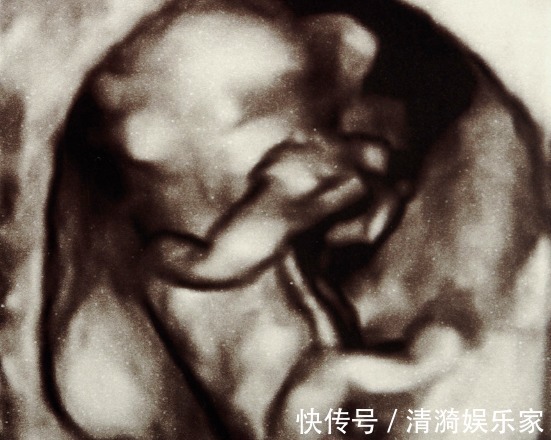

身边有一位朋友出现这个情况,怀孕之后按时产检,前几次产检胎儿很健康,完全没有问题,到孕晚期产检,却发现胎儿畸形,这让孕妈几乎崩溃。

孕前期的时候,是胎儿发育成形的重要阶段,这个时候孕妈要特别注意,尤其要注意预防胎儿畸形的出现。有些人认为只要是度过了怀孕早期就会避免流产以及胎儿畸形等多种问题了,这是一个非常错误的认识,胎儿在出生之前都是一直在不断发育的,其实有一些问题也是会在怀孕中期与晚期的时候发生的。孕22-28周,是进行胎儿畸形筛查的最佳时期,因为这个时期羊水充足,宝宝在妈妈肚子里活动空间大,宝宝大部分器官在超声下都可以观察到,能够系统完整的检测宝宝的生理发育情况,过了这个阶段孕妈才能放心。对于每个准爸爸准妈妈来说,没有什么是比能够拥有一个健康聪明的宝宝更重要的事情了。注:图片来源于网络,如有侵权,请联系删除